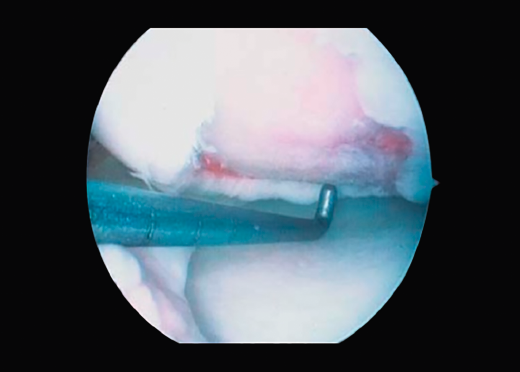

First surgery involves arthroscopy of the damaged joint. It assesses the chondral lesion to be treated and confirms whether it is amenable to the chondrocyte implantation technique (Figures 1 and 2). Other procedures are also carried out if needed, such as for example reconstruction of the anterior cruciate ligament, partial meniscectomies, meniscus implantation, patellar realignments, osteotomies, etc. Lastly, the cartilage sample is taken from a non-weight bearing zone (intercondylar zone or internal femoral condyle at its upper margin). The sample is extracted with biopsy forceps or, alternatively, using discectomy forceps. Between 3-4 rice grain-sized fragments of healthy cartilage are harvested (Figure 3). The biopsy material is placed in a sterile receptacle containing a culture medium (DMEN) (Figure 4). The material is kept at room temperature and is shipped to the laboratory as quickly as possible. A form should be completed (Figure 5), stating the joint, the location of the lesion and the size of the defect. Once in the laboratory, the sample is processed and cultured. After 4-6 weeks (depending on the case), the culture is ready for implantation.

Figure 1. Arthroscopic view of an Outerbridge grade IV acute chondral lesion of the internal femoral condyle.